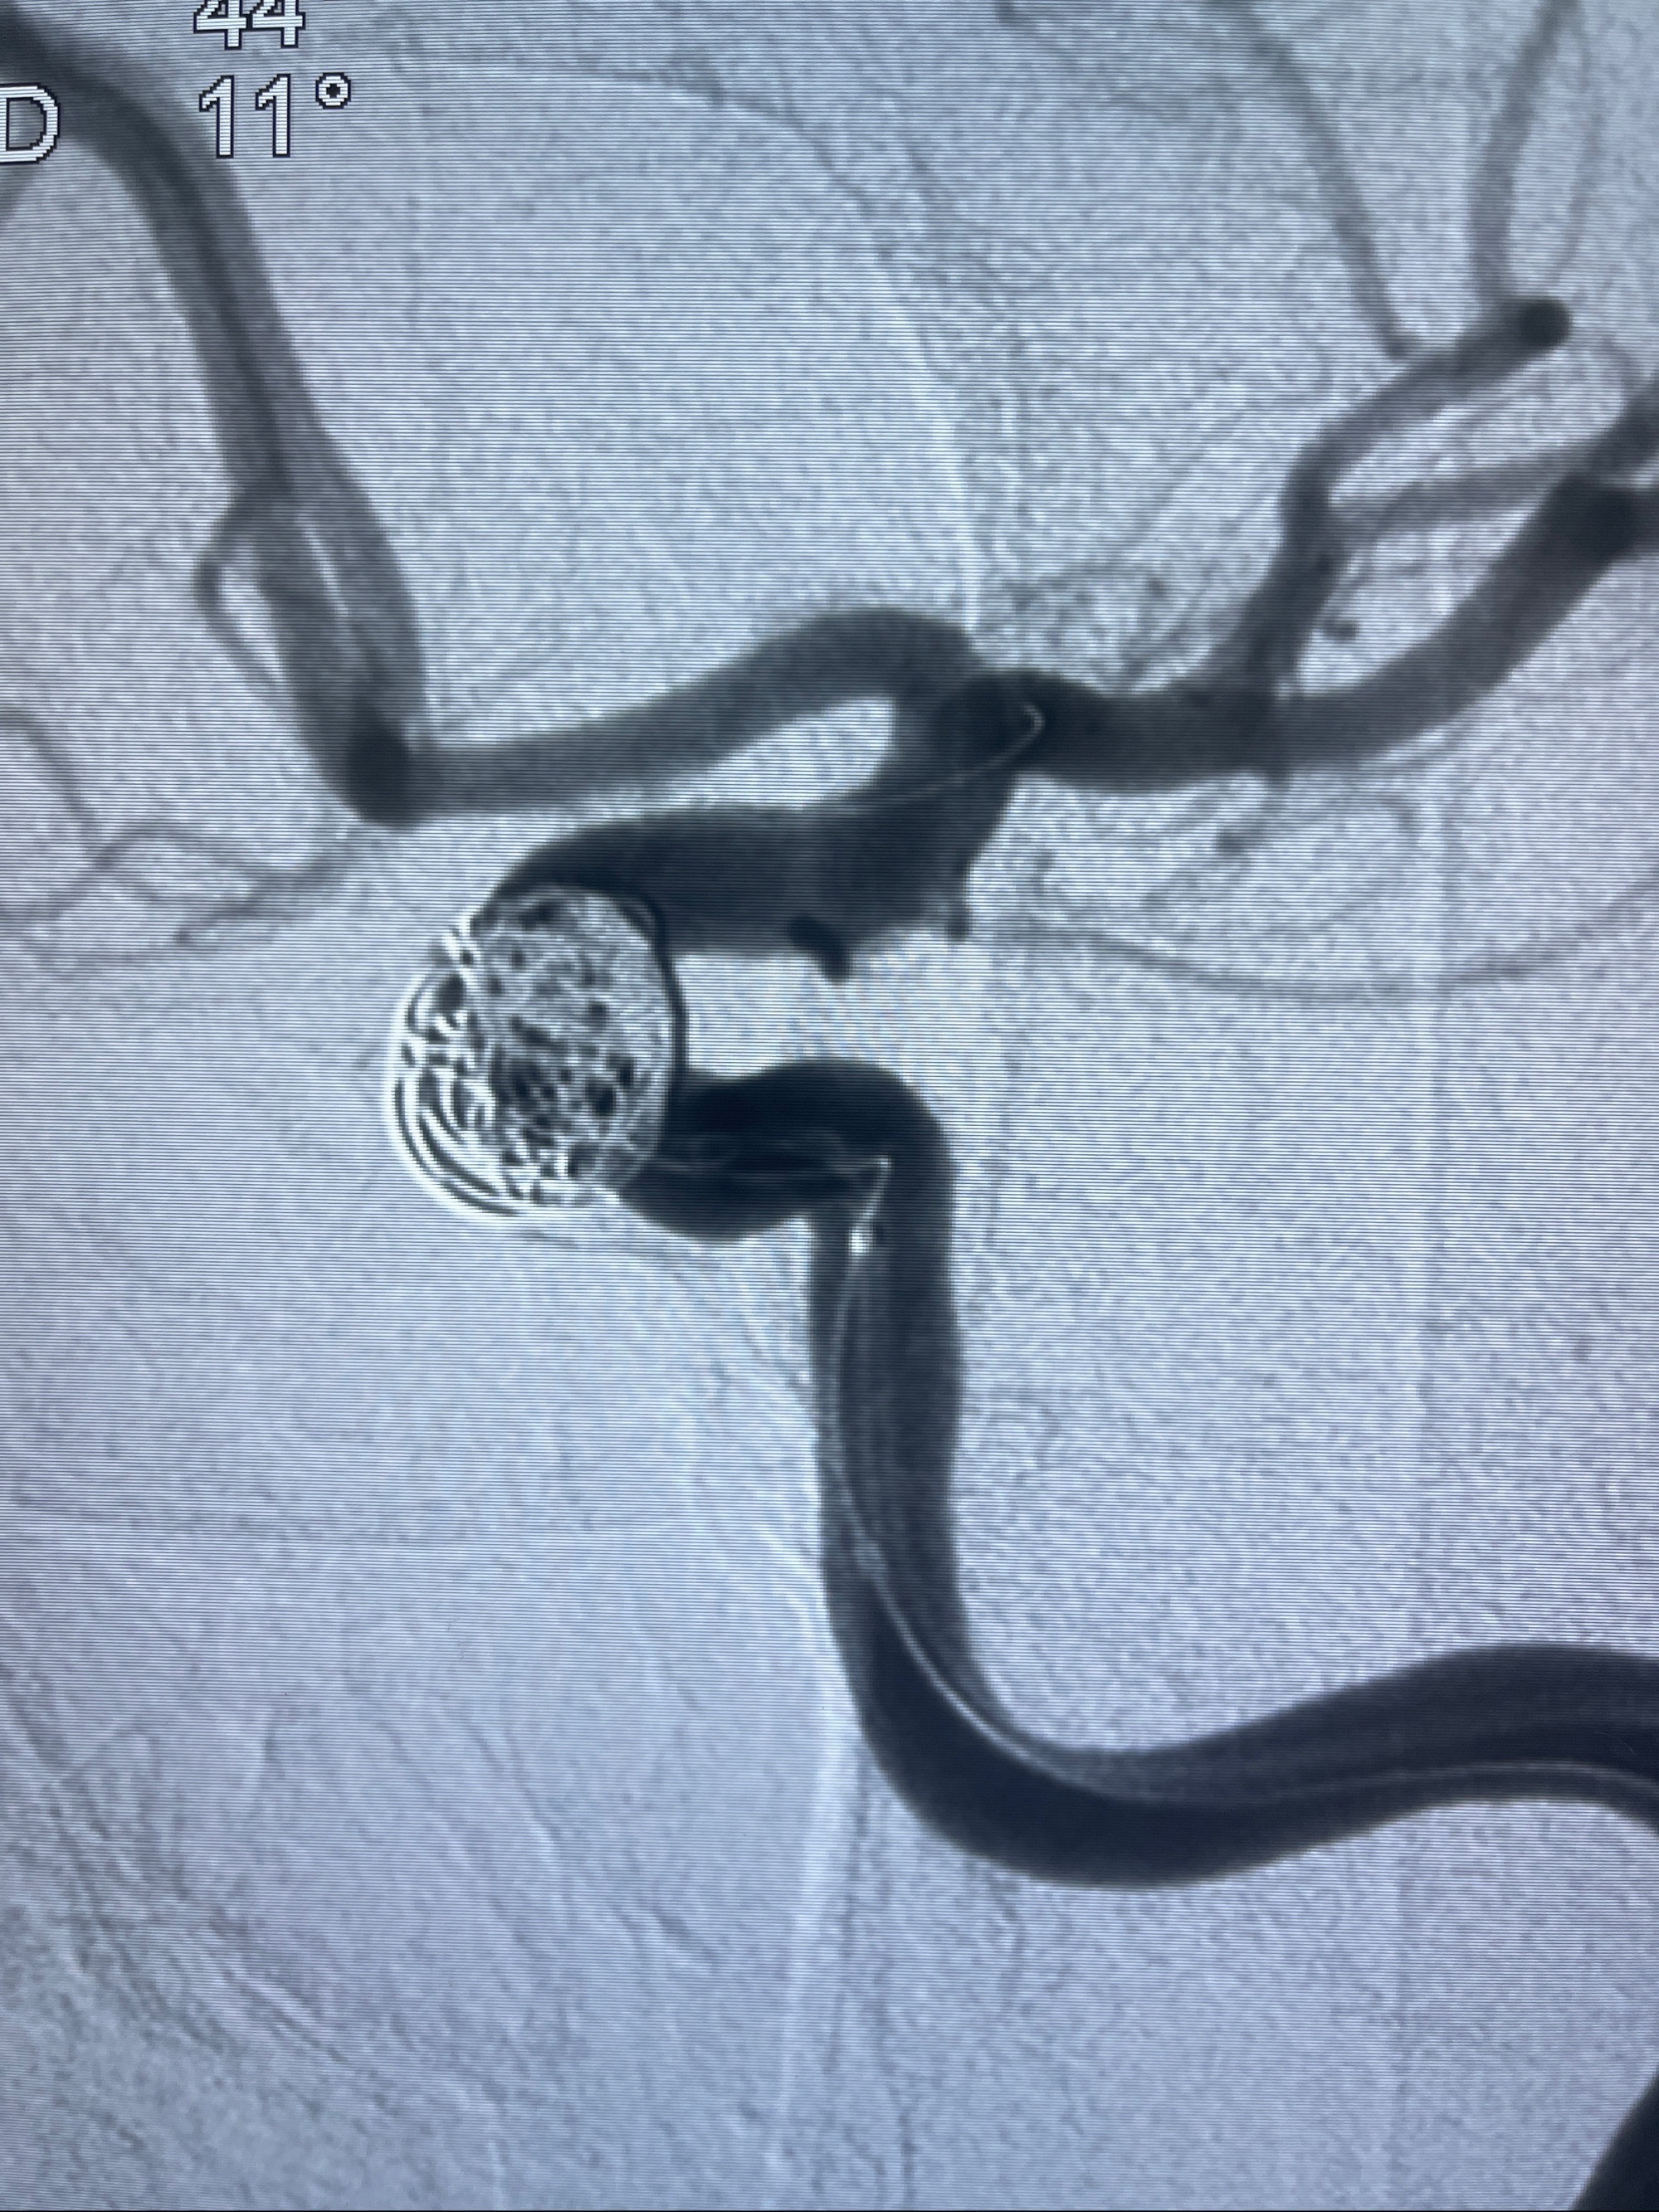

2023-08-30DSA:左侧颈内动脉眼动脉动脉瘤,约3*9.2*7.3mm大小

密网支架辅助栓塞

- Tubridge 4.0-20mm密网支架

- 加奇微弹簧圈:7*30/6*20/5*20/2*8

术后3D显示支架贴壁佳

麻醉苏醒佳,遵嘱活动!视力视野正常。